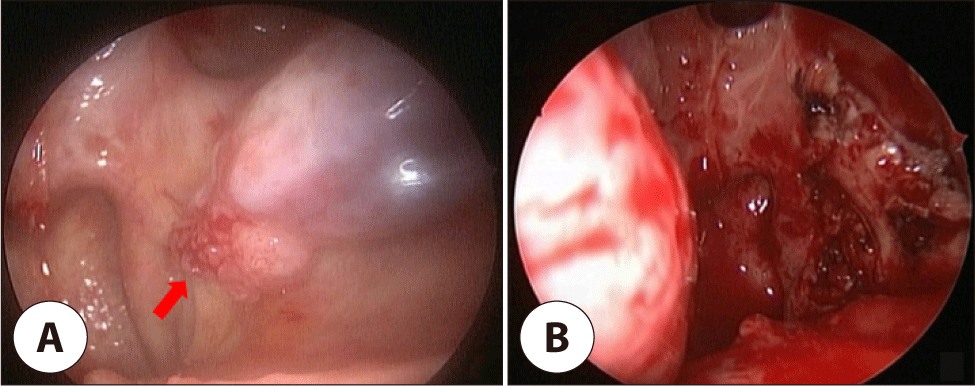

A 55-year-old male with no significant medical or social history was initially diagnosed with HPV-positive SCC of the right palatal tonsil, presenting with throat pain and blood-tinged secretion. Imaging revealed a 1.0×1.9 cm right tonsillar mass with multiple metastatic lymph nodes about 1.0–1.5 cm in the right cervical Level II (Fig. 1). He underwent right radical tonsillectomy and modified radical neck dissection, followed by adjuvant radiotherapy. Pathology revealed predominantly carcinoma in situ with severe dysplasia and equivocal minimal stromal invasion, and no recurrence was observed for 5 years.

Fig. 1. (A) Preoperative endoscopy shows a ulcerative, infiltrative mass at the right palatal tonsil (arrow). (B) Axial view of enhanced neck CT show the poorly-defined, soft tissue density mass (arrow) with heterogenous enhancement at the right palatal tonsil and cystic cervical metastatic lymph nodes at the right level II.